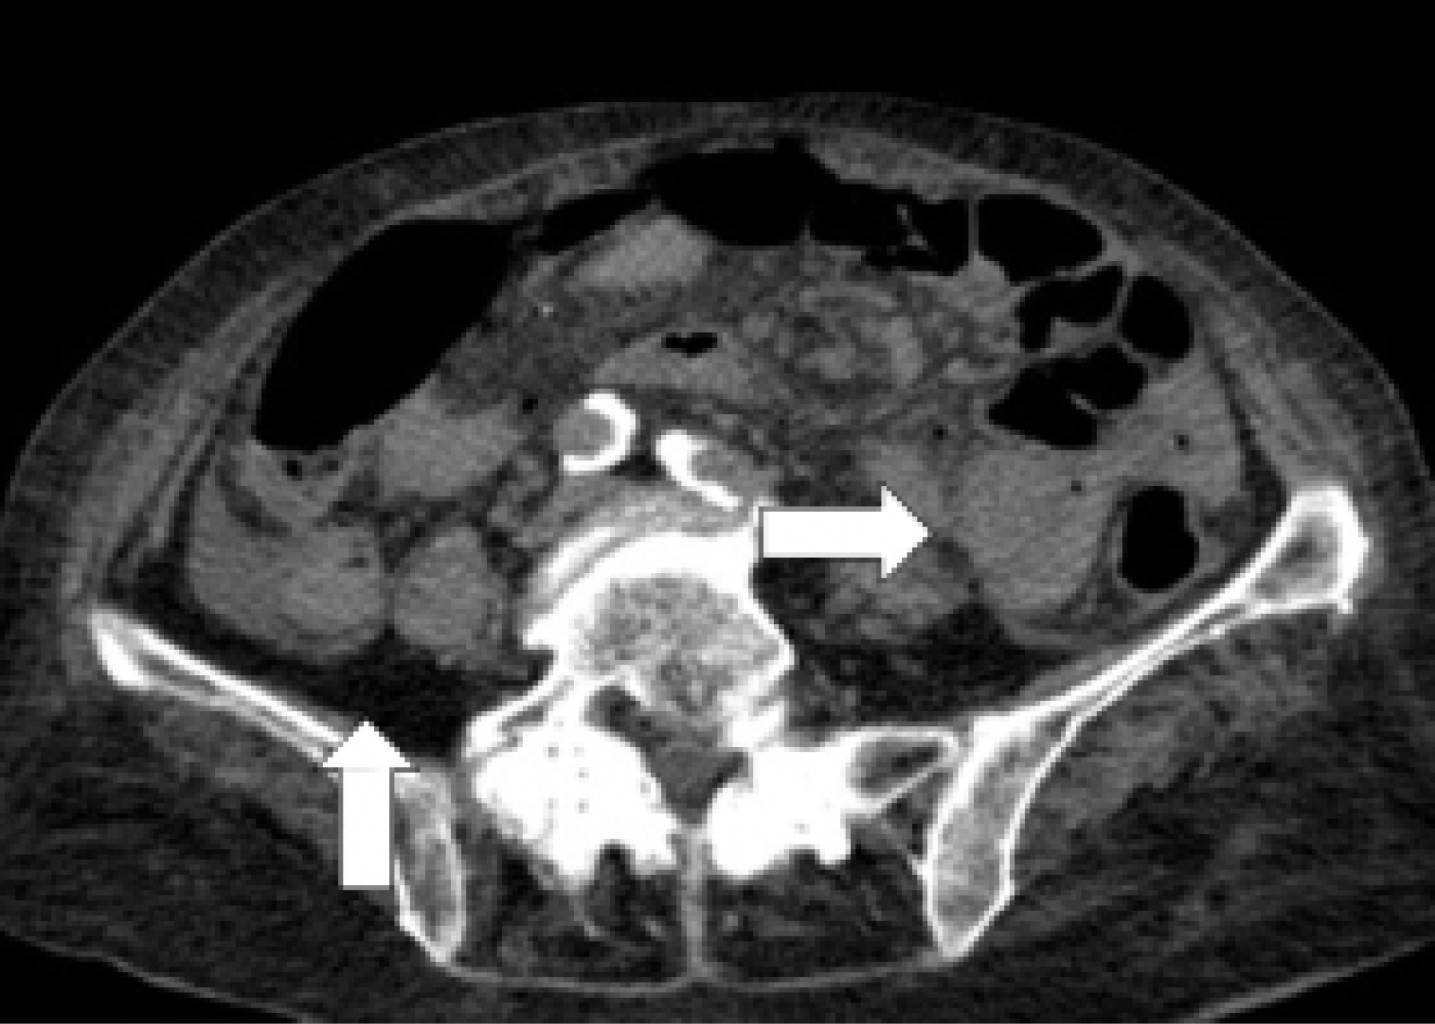

Laboratory studies reported leukopenia (3.07 × 109 l), neutrophilia (84%), hyperprocalcitoninemia (2.29 ng/ml), metabolic acidosis (pH 7.31, pCO2 27.9 mmHg, HCO3 15.8 mmHg) and hyperlactatemia (5.90 mmol/l). The rest of the laboratory tests were within normal ranges. A simple tomography of the abdomen showed pneumobilia, pneumoperitoneum, and a transition zone associated with the "whirlpool sign" in jejunum topography in a closed loop (Figure 1); and free fluid in the right parietocolic gutter (Figure 2).

Figure 3